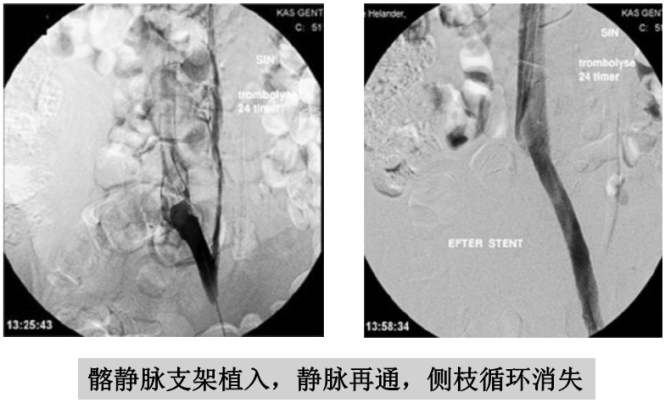

溶栓导管拔除前应做静脉造影,不仅可以判断溶栓效果,还可以发现和诊断髂静脉压迫综合征。髂静脉压迫综合征在正常人群中发生率约三分之一,在下肢深静脉血栓的病人中发生率较高。髂静脉压迫综合征一般发生在左侧,因为左侧髂静脉在生理上就位于右侧髂动脉和脊柱之间,很容易受压。这也是下肢深静脉血栓大多数发生在左侧下肢的原因。如果血栓没有完全溶解,且不准备接受髂静脉支架手术者,可以复查彩超后拔除导管。

出现髂静脉狭窄的深静脉血栓病人,如果不解除狭窄,近 期血栓完全溶解率较低,远期血栓复发率较高。所以,如果病 人经济条件许可,医院技术条件许可,在这种情况宜采取球囊 扩张、支架植入、手术修复等方法治疗。

手术的目的是减少深静脉血栓再次发生率,改善下肢静脉 回流,减少远期肢体水肿和溃烂的情况发生。一般在血栓溶解 后采取相关手术。